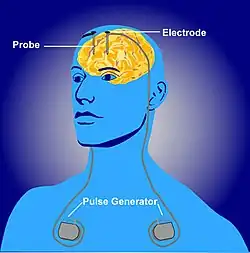

Deep brain stimulation

Deep brain stimulation (DBS) is a neurosurgical procedure which implant a tiny medical device called a brain pacemaker, which sends electrical impulses through implanted electrodes to specific area of the brain for the treatment of movement and affective disorders.The Food and Drug Administration (FDA) approved DBS as a treatment for Parkinson's disease in 2002,[80] dystonia in 2003,[81] and obsessive-compulsive disorder (OCD) in 2009.[82] DBS has been also used to treat diverse affective disorders, including major depression but these applications of DBS have yet been FDA-approved.

The deep brain stimulation system is composed of three components: the implanted pulse generator (IPG), the lead, and the extension. The IPG is a battery -powered neurostimulator enclosed in a titanium housing, which sends electrical pulses to the brain to interfere with neural activity at the target site. The lead is a coiled wire insulated in biocompatible but nondegradable polymer like polyurethane with four platinum or iridium electrodes and is placed in one or two different nuclei of the brain. The lead is connected to the IPG by the extension. It is an insulated wire that runs below the skin, from the head, down the side of the neck, behind the ear to the IPG, which is placed below the clavicle or, in some cases, the abdomen.[83]The leads are placed in the brain according to the type of symptoms to be addressed. The IPG can be calibrated by a neurologist,nurse, or trained technician.[84]

All three components are surgically implanted in the brain. Lead implantation may cause local anesthesia or general anesthesia ("asleep DBS"). A hole about 14 mm in diameter is drilled in the skull and the probe electrode is inserted. During the awake procedure with local anesthesia, feedback from the patient determines the best placement of the permanent electrode. During the asleep procedure, intraoperative MRI guidance is used for the determination of the electrode. [85] Generally, the IPG and extension leads are installed under general anesthesia.[86]